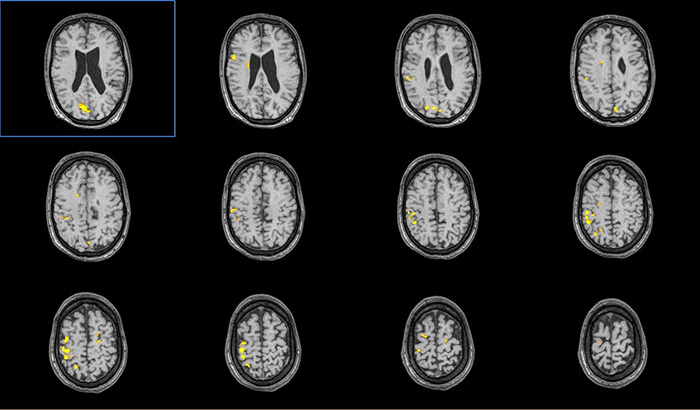

Цель: Апробация и внедрение в клиническую практику современных методик фМРТ и DTI для оценки структурных и функциональных изменений при нарушениях движения у детей. Описание проекта: Для Детского Церебрального Паралича характерно наличие незначительных структурных повреждений [1], при этом неясна их связь с нарушениями двигательных функций. фМРТ позволяет выявить зоны активации мозга при выполнении движений и оценить сложность выполнения задания по объему зон активации (Рис 1). МР-трактография позволяет исследовать структуру и диффузионные характеристики проводящих путей мозга (Рис 2). МР-волюметрия также позволяет оценить объем основных структур мозга и выявить аномалии развития, кортикальные дисплазии и патологии белого вещества мозга (Рис 3.). Результаты: Проведена клиническая апробация предложенных методик. Результаты представлены на медицинских неврологических конгрессах.

Рис. 3. МРТ данные пациента с ДЦП: на FLAIR изображениях структурные изменения минимальны.